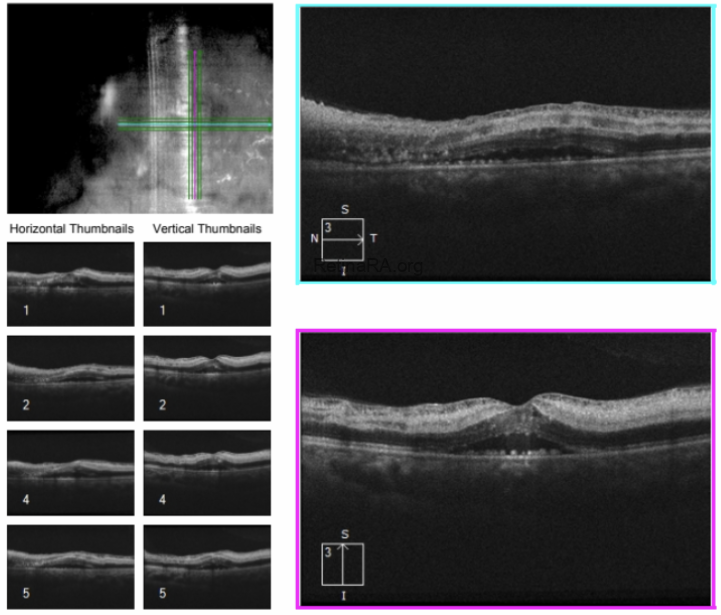

A patient presented with a complaint of sudden loss of vision in the right eye. Fundoscopic examination revealed mild venous dilatation and tortuosity, optic disc edema, flame-shaped retinal hemorrhages around the disc, cotton-wool spots (soft exudates) in the nasal quadrant, and lipid exudates (hard exudates) forming a macular star pattern around the fovea. Additionally, the superior temporal quadrant of the retina was noticeably pale, and there was mild paleness around the inferior temporal branches of the retinal vein (white arrows).

Based on the clinical findings, the patient was diagnosed with SLE-associated neuroretinitis (stellar) and BRAO. The pallor around the inferior temporal vein branches was interpreted as perivenular fern-like PAMM (white arrows). Furthermore, the presence of venous dilatation, vascular tortuosity, and perivenular fern-like PAMM suggested that, although the patient did not have complete CRVO, there may have been a partial occlusion of the central retinal vein due to optic nerve head stasis.